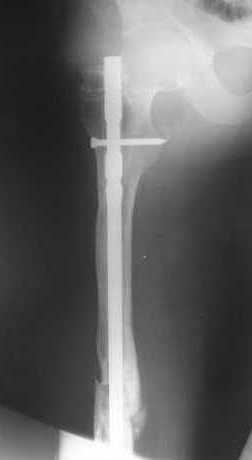

В приложении как раз видна эволюция использововшихся у нас большеберцовых гвоздей. Первый - дизайн как у UTN, второй - разнесены 45 градусные отверстия (зачем их вообще изначально так нелепо на одном уровне сделалм???), третий - убрано сиавшее лишним статическое отверстие, Herzog's bend перемещен более проксимально.